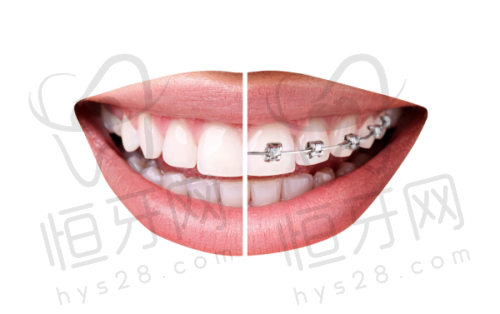

正畸项目:正畸也是门诊部的热门项目。对于牙齿不齐、咬合不正等问题,正畸治疗可以有效地改善牙齿的排列和咬合关系,不仅能提升面部美观度,还能促进口腔健康。门诊部提供了多种正畸方案,如传统金属托槽矫正、陶瓷托槽矫正、隐形矫正等,患者可以根据自己的需求和经济状况选择适合自己的矫正方式。医生们会在治疗前进行详细的口腔检查和分析,制定个性化的矫正方案,确保矫正成效达到至佳。

评价三:“我家孩子牙齿不齐,我一直想给他做矫正。经过多方比较,我选择了衢州开化可恩口腔门诊部。医生根据孩子的口腔情况,为他推荐了隐形矫正方案。这种矫正方式特别美观,孩子也特别容易接受。在矫正过程中,医生会定期调整矫正方案,确保矫正成效。现在孩子的牙齿已经有了明显的改善,相信继续矫正下去,一定会达到理想的成效。而且,门诊部的环境良好,孩子每次来都不觉得害怕。”